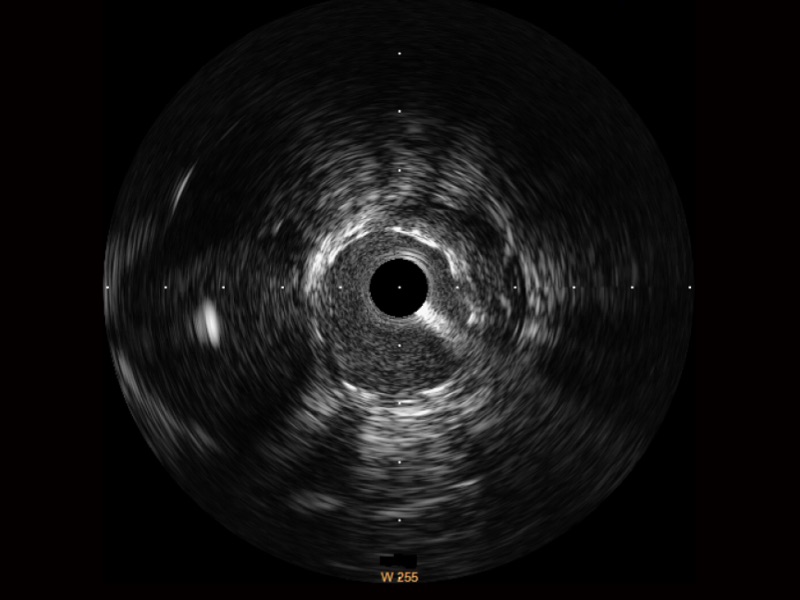

临床图

支架内血栓